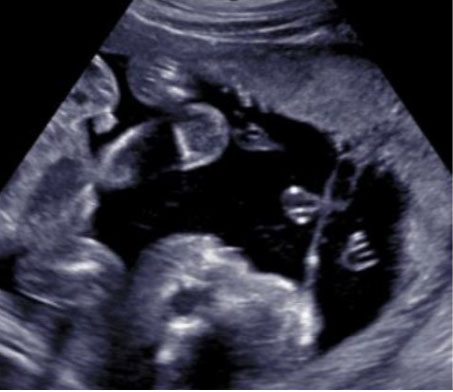

A routine fetal ultrasound assessment performed at 19 weeks’ gestation revealed right lateral encephalocele (Figure 1), large right cleft lip and palate with the defect expanding to the right eye socket, left lower extremity edema, and bilateral rocker-bottom feet (Figure 2, Figure 3, Figure 4). The patient underwent an amniocentesis at 20 weeks gestation that revealed normal male karyotype and normal microarray, without any maternal cell contamination. Repeat ultrasound at 23 weeks gestation showed previous anomalies with appearance of a thick right lateral amniotic band spanning the full length of the skull and facial defects as well as bilateral clenched fists (Figure 5). Fetal echocardiogram done at that time was without any evidence of structural cardiac abnormalities. She underwent extensive consultation in regard to ABS and outcomes, with plans for close follow-up. She presented at 26 weeks gestation for her scheduled growth scan reporting decreased fetal movement. She was diagnosed with intrauterine fetal demise measuring in the 9th percentile with an estimated fetal weight of 768 grams. She was admitted for induction of labor and went on to have an uncomplicated vaginal delivery. After delivery, fetal examination revealed profound midfacial deformities, brachydactyly, and placental adhesions. Placental pathology significant for a 20.7 cm long three vessel, peripherally inserted, umbilical cord with amnion constriction near placental insertion. Fetal membranes displayed features of amnion/chorion disruption as well as thickened bands of chorionic connective tissue and extraembryonic celom between the amnion and the chorion. These findings were somewhat difficult to fully discern due to the breakdown of fetal tissue after the intrauterine fetal demise.

Figure 5: Addition amniotic band contact area.